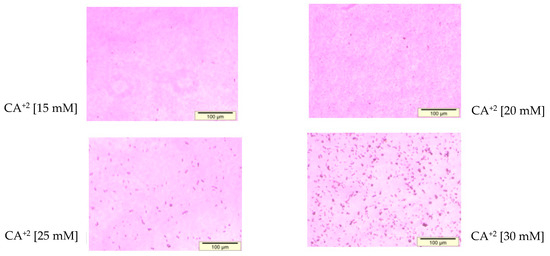

3.1. Optimization of CA NPs Based on Turbidity, Particle Size, and Cytotoxicity Profiling